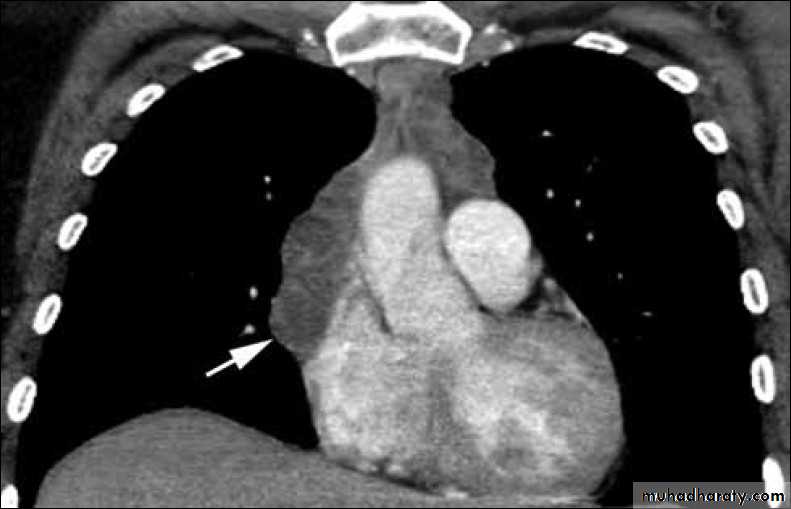

Bronchogenic cyst

Vascular and chest surgery practical